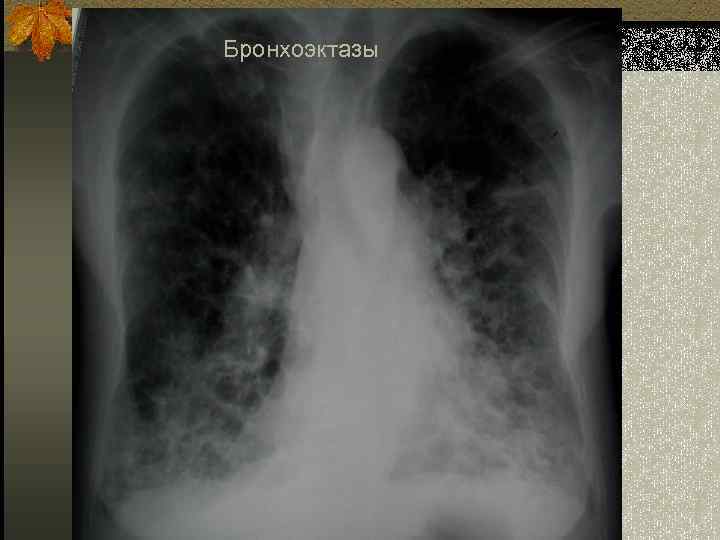

Бронхоэктазы